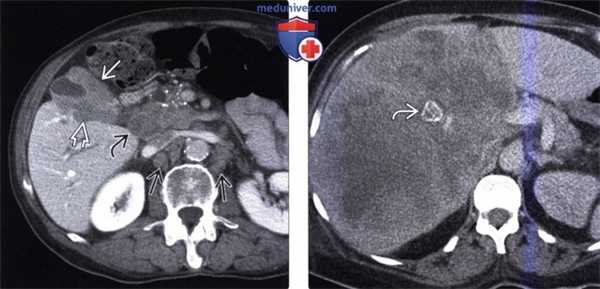

(Слева) На корональной КТ с контрастным усилением (объемный рендеринг) определяется симптом «двойного протока» на фоне обструкции общего желчного и печеночного протоков, обусловленной полиповидным объемным образованием (рак) ампулы фатерова сосочка.

(Справа) На корональной КТ с контрастным усилением визуализируется дискретное объемное образование вокруг ампулы фатеровы сосочка, в которой находится билиарный стент. Рак ампулы сложно отличить от периампулярного рака двенадцатиперстной кишки методами визуализации, но, тем не менее, лечение в обоих случаях одинаково (операция Уиппла).

(Слева) На корональной КТ с контрастным усилением в ампуле фатерова сосочка визуализируется объемное образование округлой формы, с четкими контурами, приводящее к обструкции общего желчного протока. Рак ампулы практически всегда приводит к обструкции общего желчного протока, однако обструкция панкреатического протока возникает только в 50% случаев.

(Справа) На аксиальной КТ с контрастным усилением визуализируется инвазивная аденокарцинома ампулы фатерова сосочка, возникшая из ворсинчатой аденомы. Обратите внимание на циркулярное объемное образование большого размера (в виде «огрызка яблока») двенадцатиперстной кишки, располагающееся на границе ее второй и третьей части.